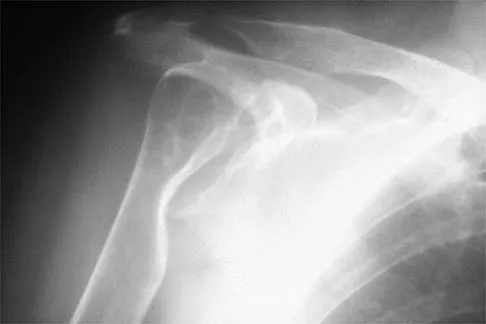

A 79-year-old woman with polyarticular rheumatoid arthritis has had progressively increasing right shoulder pain for the past year, and nonsurgical management has failed to provide relief. Her neurologic examination is entirely normal, but she is unable to elevate her arm against gravity. An AP radiograph is shown in Figure 13. Treatment should consist of

Explanation